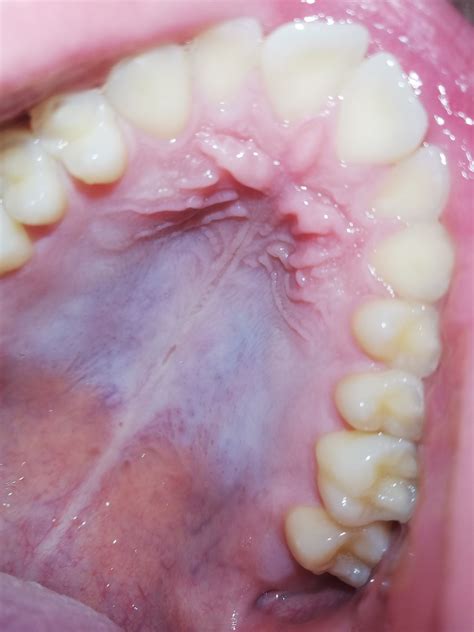

The roof of the mouth, also known as the palate, is divided into two parts: the hard palate and the soft palate. The hard palate is the bony front portion, while the soft palate is the muscular back portion. The hard palate is covered by a mucous membrane, which can sometimes develop discolorations, including a white roof of mouth.

• Leukoplakia: This condition involves thick, white patches that can develop on the roof of the mouth and other areas inside the mouth. It is often painless but can be a sign of precancerous changes.

• Lichen Planus: This is an inflammatory condition that can cause white lines or patches on the roof of the mouth and other mucous membranes.

• Oral Lichen Planus: This is an inflammatory condition that can cause white lines or patches on the roof of the mouth and other mucous membranes.